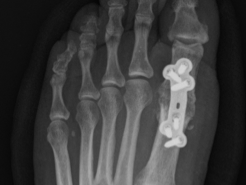

1st MTP Fusion

1st MTP Joint Fusion - Hallux Rigidus

Surgery to correct a painful, unstable or arthritic 1st metatarsophalangeal joint. Read more >>